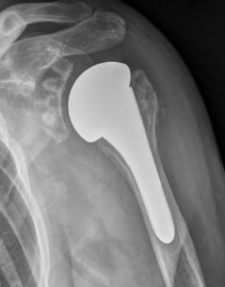

Prothèse inversée

Elle est indiqué pour les arthrose excentré avec des tendons rompus